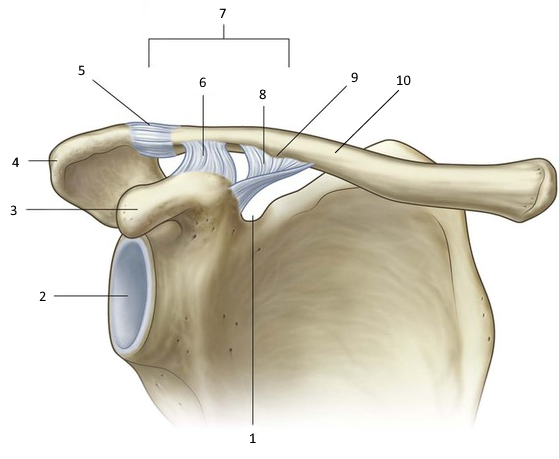

РОЗПІЗНАЙТЕ ДОДАТКОВІ ЕЛЕМЕНТИ ЦЬОГО СПОЛУЧЕННЯ.

варіанти відповідей

ДИСКИ

МЕНІСКИ

СУМКИ

БУРСИ

ЗВ'ЯЗКИ